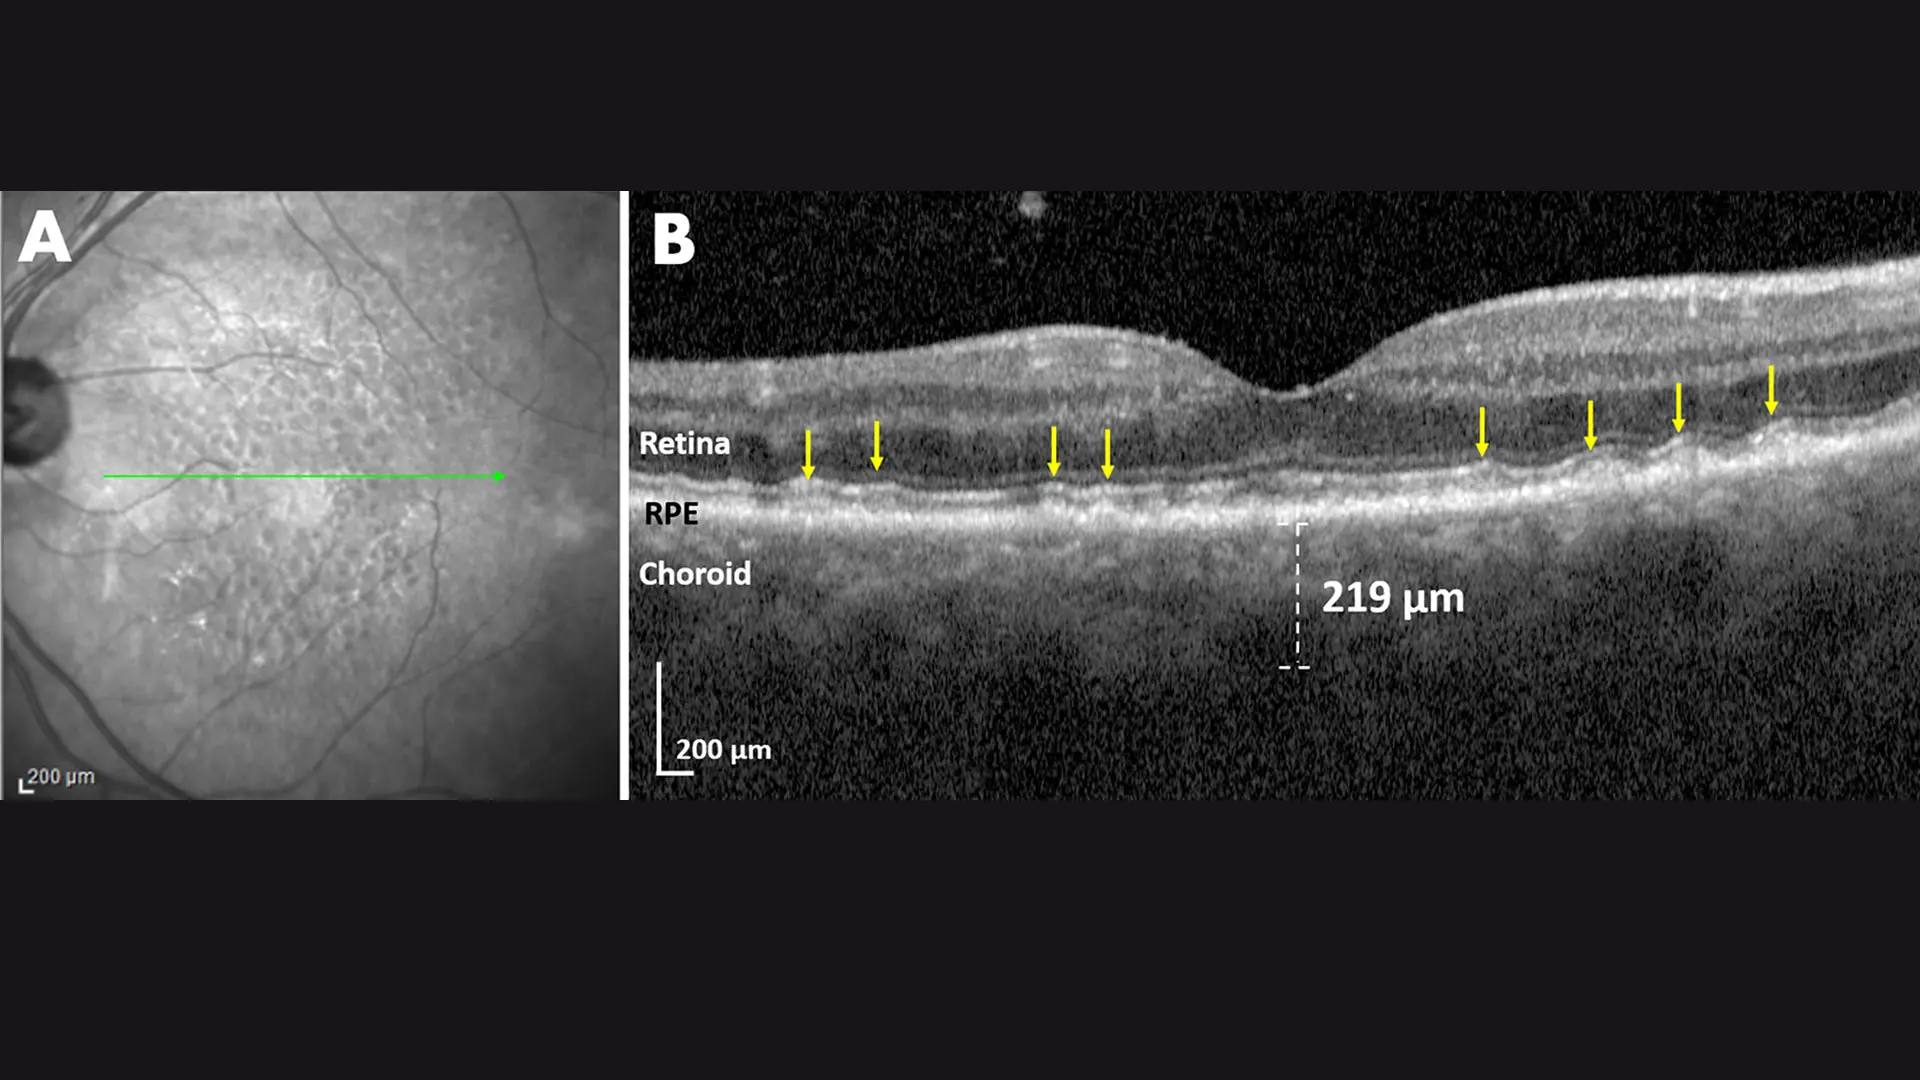

Fig. 3: Severe Aortic Stenosis

Left Eye

Infrared scan: Multiple homogeneous dark lesions of SDD. Green line: Location of OCT scan. OCT scan: Multiple SDD (yellow arrows) in several smooth, wave-like series. The measured choroidal thickness of 219 microns corrected for hyperopic refractive error is ~169 microns, more typical for SDD. The right eye had been lost to glaucoma and vascular disease. Aortic stenosis is an example of a cardiovascular disease unrelated to atherosclerosis, but compromising cardiac output and ophthalmic perfusion, hence causing SDDs.